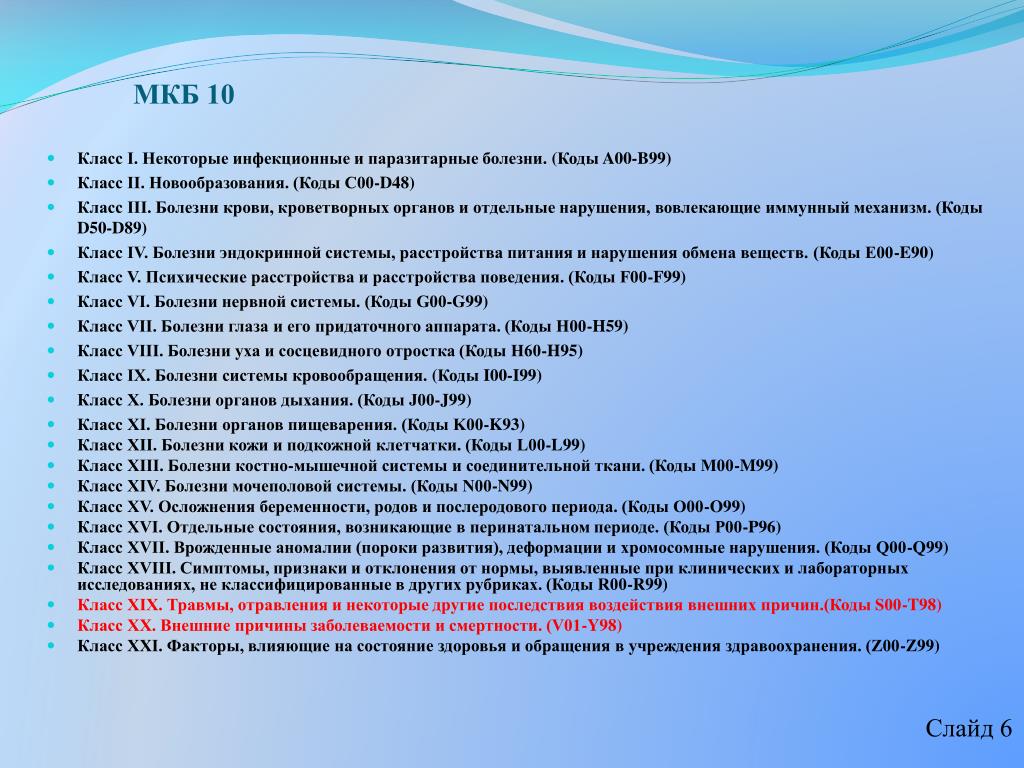

Острая внебольничная пневмония по МКБ-10: признаки и примеры